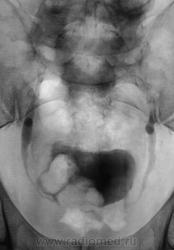

Мочевой пузырь с дефектами наполнения. А что на УЗИ?

Плюс мелкие интенсивные тени над 12 ребром слева, опять калькулезный панкреатит?

Интересно: в мочевом камни или образование?

Пациент, уже в урологическом отделении ОКБ, готовится к операции.